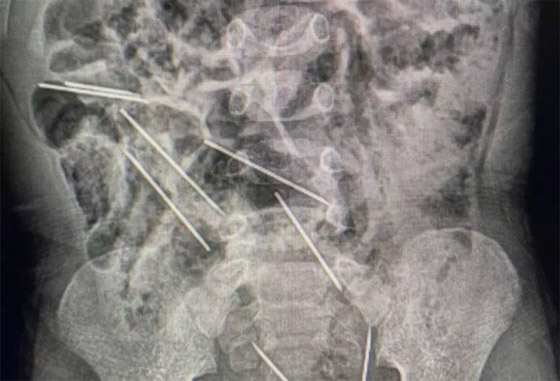

كيف فعلها؟ طفل يبتلع 8 إبر حقن والأطباء يتدخلون بـ"فتح بطنه"!

أنقذ أطباء في شمال شرق بيرو حياة طفل عمره عامان، بعد أن ابتلع 8 إبر حقن وهو يلعب. وقال الطبيب إفراين سالاسار في تصريحات: "عندما كنا في غرفة العمليات وفتحنا بطنه وجدنا تلك القطع المعدنية، وأدركنا أنها كانت في الحقيقة إبرا". وذكرت وسائل إعلام محلية أن الإبر كانت من تلك التي تستخدم لتطعيم حيوانات، بمزرعة تعمل فيها والدة الطفل.

ويعيش الطفل، الذي لم يتم الكشف عن اسمه، في منطقة تاراتوبو الزراعية، على بعد حوالي 622 كيلومترا من العاصمة ليما. وقالت والدته: "ربما ابتلعها عندما كان يلعب هناك". وذكرت وسائل إعلام محلية أن حياة الطفل ليست في خطر بعد الجراحة.